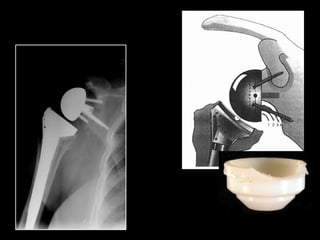

Grammont Type Reverse

(France 1987)

Grammont P, Trouilloud P, Laffay JP, et al. Etude et realisation d’unenouvelle

prothe`sed’e`paule.Rheumatologie. 1987;39:407–418. [French]

DESIGNS

Grammont Type Reverse (France1987) Grammont P, Trouilloud P, Laffay JP, et al. Etude et realisation d’unenouvelle prothe`sed’e`paule.Rheumatologie. 1987;39:407–418. [French]